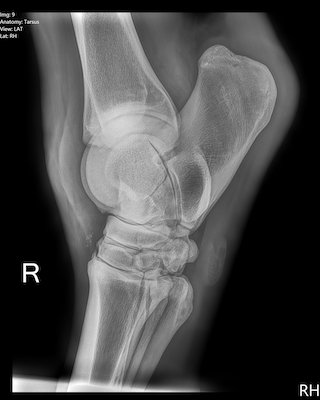

A nine-year-old Quarterhorse mare is presented with a right hind limb lameness.

She tends to drag the right toe, and has a stabbing gait in that limb (adducts hindlimb, then suddenly abducts it just before the hoof hits the ground).

Hock flexion of the right hind significantly exacerbates the lameness for five to six strides. A radiograph of the hock is taken, shown below.

What is the common name for this problem?